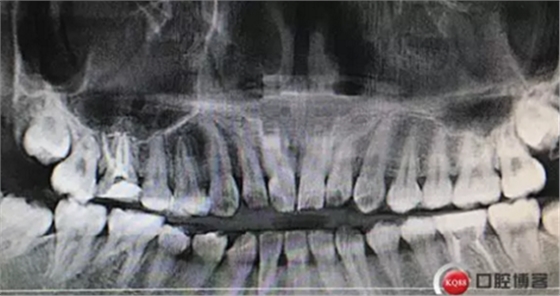

牙列完整,后牙中性關(guān)系,前牙開合,中線對齊。16合面大面積齲壞,內(nèi)褐色腐質(zhì),冷診無反應(yīng),叩痛(+-)。36合面樹脂充填,充填物在位,頰側(cè)冠折,折線位于齦緣下,冷診無反應(yīng),叩痛(+)。其他無殊。

治療計劃:36局麻下拔除碎片,攝片檢查余留牙體組織。16完善根管治療,擇期修復(fù)。

根管治療完成攝片

治療完成,聚羧酸鋅水門汀暫封觀察一周,后期常規(guī)根管樁全冠修復(fù)。同期16治療完成。